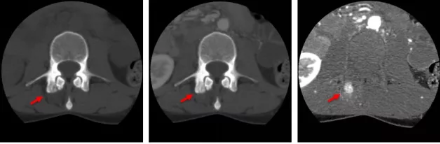

骨智能柔性減影成像功能發(fā)現(xiàn)隱匿骨占位病灶

相比傳統(tǒng)成像方式,肺部柔性減影技術(shù)通過人工智能,對平掃數(shù)據(jù)和CT肺動脈血管掃描數(shù)據(jù)進行智能比對,解碼并識別各個器官(肺、氣管、肺動脈、肺靜脈、主動脈等)的空間位置,并在三維空間中進行體素級的柔性配準,從而極大提升了不同序列數(shù)據(jù)的空間位置的一致性。通過肺部柔性減影技術(shù)可得到肺強化碘圖,可以顯示出傳統(tǒng)CTPA圖像看不到的小栓塞病變,提高了栓塞檢出率,其結(jié)果甚至可與SPECT吻合。

肺智能柔性減影成像功能發(fā)現(xiàn)亞段肺栓塞